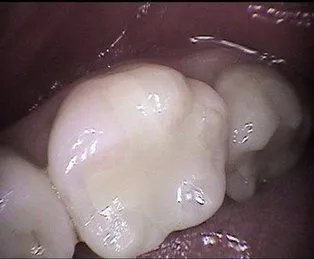

Root Canal Treatment

Before

After